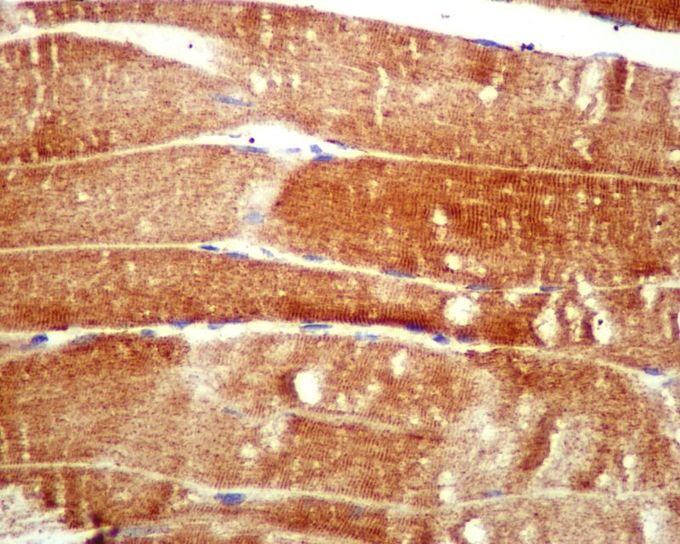

IHC-P analysis of human skeletal muscle tissue using Atg4A antibody [EPR4122] at a dilution of 1:100.